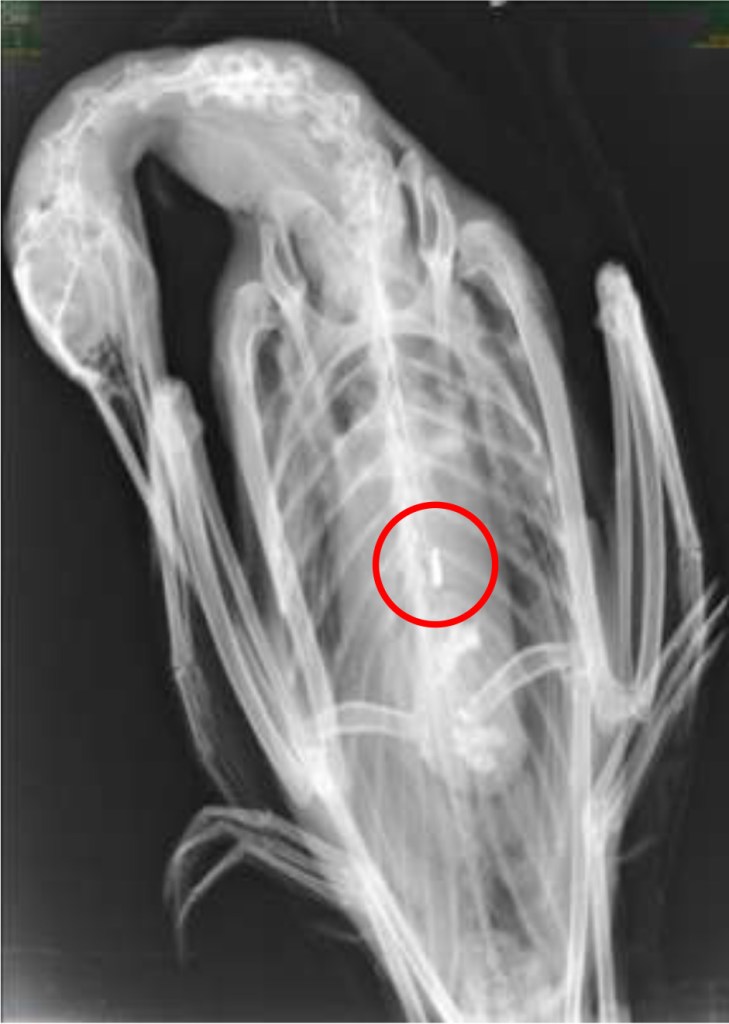

Radiograph of Common Loon TV10-138, showing an ingested lead jighead (circled). Recovered from Toddy Pond in Orland, ME on Sept. 7, 2010. (Source: Mark Pokras, Tufts Veterinary School)